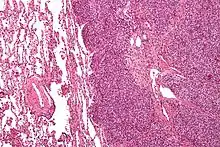

Micrograph of metastatic Ewing sarcoma (right of image) in normal lung (left of image). PAS stain.

Micrograph of a metastatic Ewing sarcoma with the characteristic cytoplasmic clearing on H&E staining, which was showing to be PAS positive

The definitive diagnosis is based on histomorphologic findings, immunohistochemistry and molecular pathology.

Ewing sarcoma is a small-blue-round-cell tumor that typically has a clear cytoplasm on H&E staining, due to glycogen. The presence of the glycogen can be demonstrated with positive PAS staining and negative PAS diastase staining. The characteristic immunostain is CD99, which diffusely marks the cell membrane. However, as CD99 is not specific for Ewing sarcoma, several auxiliary immunohistochemical markers can be employed to support the histological diagnosis.[23] Morphologic and immunohistochemical findings are corroborated with an associated chromosomal translocation, of which several occur. The most common translocation, present in about 90% of Ewing sarcoma cases, is t(11;22)(q24;q12),[24][25] which generates an aberrant transcription factor through fusion of the EWSR1 gene with the FLI1 gene.[26]